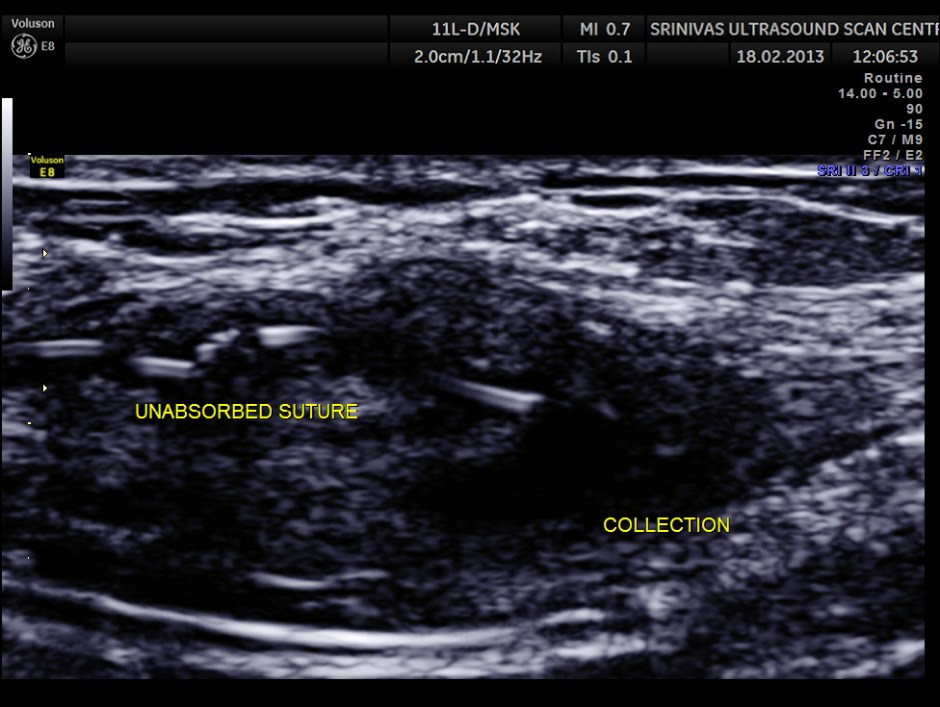

Her routine abdomino pelvic ultrasound scan was normal. The following pictures are acquired with a high resolution 11Mhz transducer.

This revealed unabsorbed suture and irregular collection

She was taken up for exploratory procedure to remove the suture remnants.